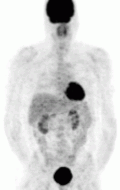

MIBG Scintigraphy — the pheochromocytoma is appreciated in the left panel on the right side of the screen (right panel; left side of the screen) as the darkened circle towards the abdomen. The darkened structure at the head of the patient is the thyroid gland, while the darkened structure in the pelvis of the patient is the bladder. This is normal physiologic uptake.

The first functional imaging technique utilized in pheochromocytoma patients was 123I-MIBGscintigraphy. Given the compound's similar structure to the catecholamine norepinephrine (secreted by pheochromocytomas), MIBG was well-suited for uptake by most neuroendocrine tumors.[94] Furthermore, if a patient was found to be positive on an MIBG scan, they were eligible for MIBG treatment, offering additional avenues for those with widespread metastatic disease.[95] However, further investigation revealed that while MIBG excelled with adrenal lesions, it was far less superior in patients with extra-adrenal paragangliomas, particularly with specific genetic variants like those in the succinate dehydrogenase subunit–encoding genes (SDHx).[83] As the positron emission tomography scans were developed, MIBG has slowly lost its favor for the pheochromocytoma patient.[83]

FDG PET — the tumor is appreciated as the dark structure in the patient's left chest. The darkened structure at the head of the patient is the brain, posterior to the abdomen are the kidneys, and in the pelvis is the bladder. These are normal.

Of the four above mentioned modalities, 18F-FDGPET is the most common and readily available functional imaging technique at most hospital systems, but the least-specific to neuroendocrine tumors (Image Left). In 2012, over 200 patients participated in a trial that compared the current gold standard of the time (MIBG/CT/MRI) to the novel FDG PET. Compared to its functional counterpart, FDG outperformed MIBG in detecting soft-tissue and bone metastases with higher specificity in patients with biochemically active tumors.[83]